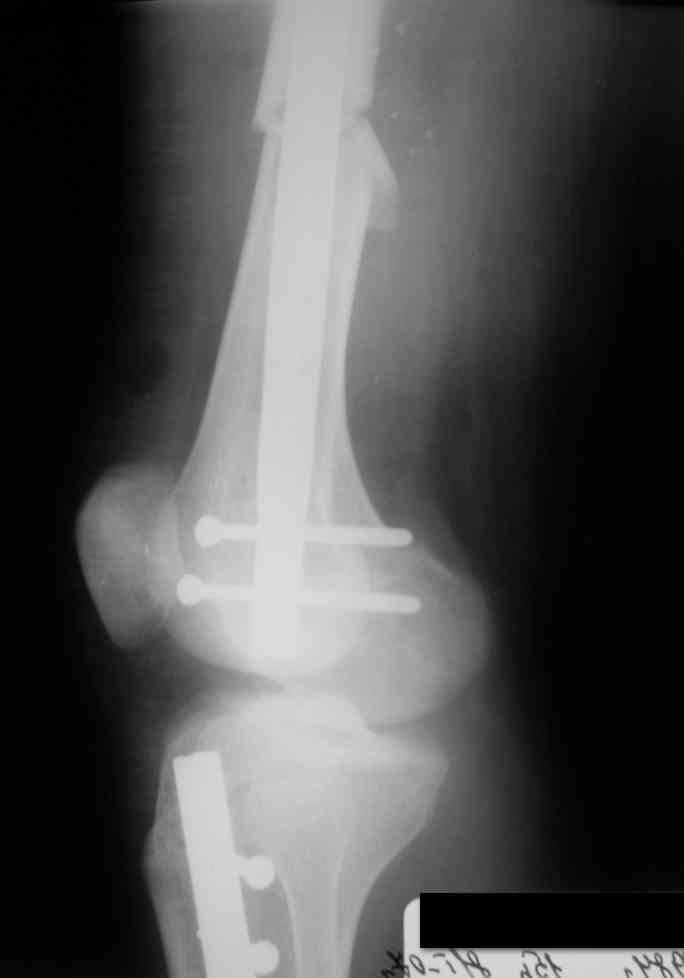

Вчера первый раз синтезировали голень гвоздем Fixion.

Спиральный оскольчатый перелом, ниже середины, у молодого парня. Сделали "классический" вариант гвоздя, который еще без винтов. Получилось все легко. Не торопясь, сделали операцию минут за 20. См. фото.

Дорогой Александр. Имею скромный опыт использования системы Fixion при переломах плеча, бедра и тибии. Всего 18 наблюдений с сентября 2006 г. Результаты отличные. Гвоздь индивидуален для каждого медуллярного канала. Легко имплантируется как в узкий, так и в деформированный канал. Это позволяет применять метод интрамедулярного остеосинтеза без ненужных потерь времени операции, флюороскопии и реально снижает крвопотерю и операционный риск. Удаление происходит без проблем. Особенно интересны больные с ипсилатеральными переломами бедра и голени.

В отношении ранней нагрузки при спиральных переломах лучше не торопиться. По данному случаю необходимо достигнуть исчезновения щели между штифтом и внутреним кортексом по Rg. А так картинка прекрасная - и длина сегмента и репозиция. Можно поздравить, коллега!

Да, спасибо за интересные иллюстрации. Получилось очень симпатично. На большеберцовой кости непременно надо было винты? Там же был торцовый упор, перелом в средней трети?